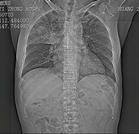

其他輔助檢查:

1.內鏡檢查 常見食管黏膜充血、水腫、潰瘍、假膜及局部脆性增加。